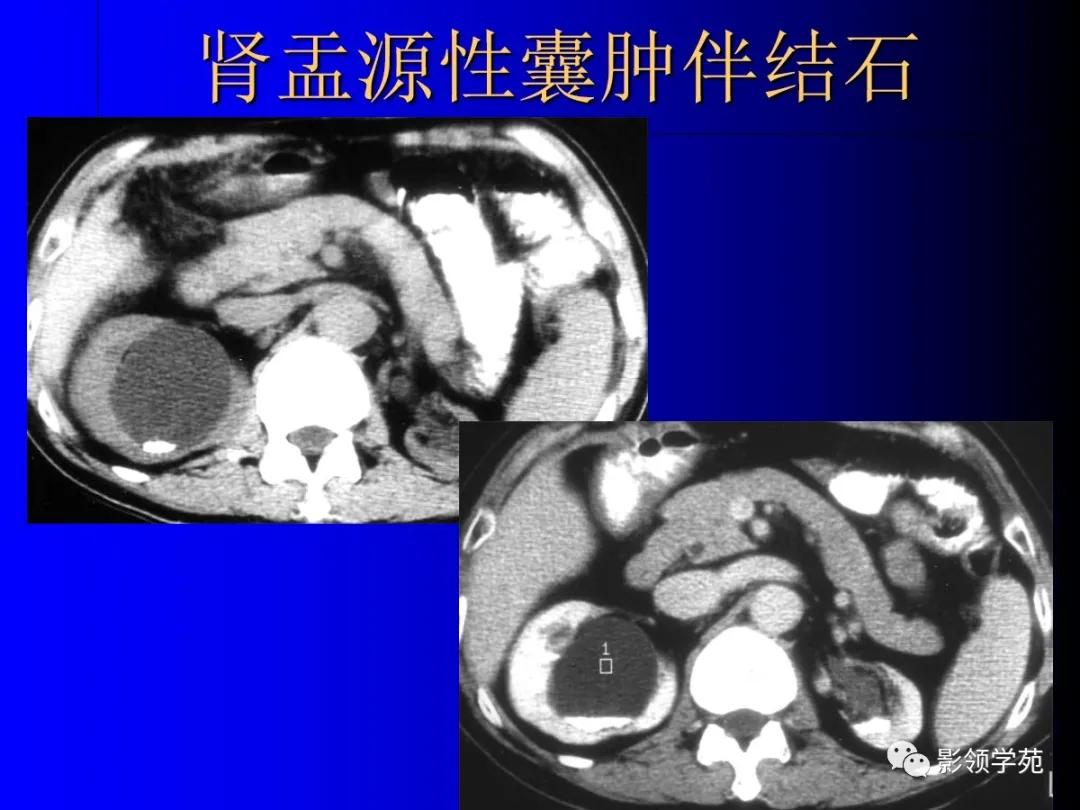

3、肾盂源性囊肿(肾盏憩室)

肾内囊性占位,和肾盂肾盏相通。

-

增强后造影剂进入囊肿。

囊肿内结石发病率高。

肾盂源性囊肿较大,偏中央。

肾盏憩室较小,偏周围。